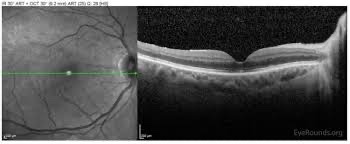

Через месяц после операции оптическая когерентная томография показала, что органоид заполнил место разрыва. В течение трех месяцев не наблюдалось признаков отторжения, а анализы показали активность фоторецепторов. Однако спустя четыре месяца возник небольшой отек органоида, который прошел после введения стероидных противовоспалительных препаратов. В дальнейшем глаз был извлечен, и было подтверждено нормальное приживление органоида.